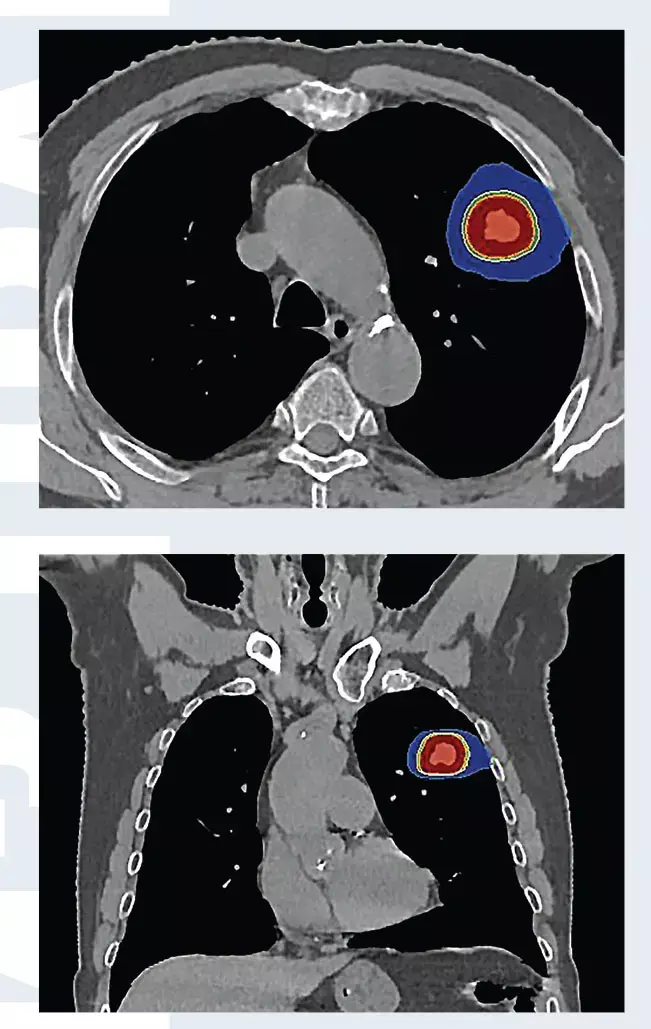

Установлен диагноз периферического рака верхней доли левого легкого cT1bN0M0, Ia стадия. В связи с выраженной сопутствующей кардиологической патологией и высоким риском осложнений хирургическое лечение не проводилось. Пациенту проведено три сеанса СЛТ с разовой дозой 18 Грей за сеанс, с интервалом через 1 день (рис. 1). По данным ПЭТ/КТ через 4 месяца после лучевой терапии опухоль уменьшилась в размерах, перестала накапливать фтордезоксиглюкозу (рис. 2). Имеет место полный метаболический ответ опухоли на лечение.

Рис. 1. План стереотаксической лучевой терапии при периферическом раке левого легкого. Максимальная доза облучения (красным цветом) подводится локально на опухоль, окружающие нормальные ткани практически не облучаются.